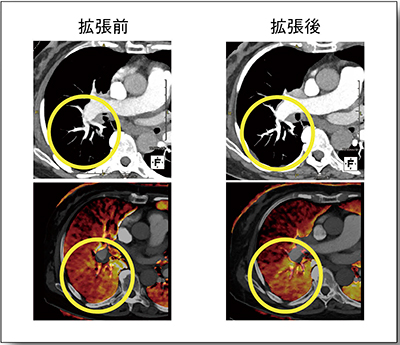

症例によっては,血管拡張術の治療前後の3D-CTAを比較すると,一見して治療した末梢領域の灌流が改善していることがわかる(図7)。しかし,症例5では,治療前CTAではスリット状の狭窄病変を認識しにくく,治療前後を比較しても効果判定は容易ではない(図8上段)。それに対してLung PBVは,治療前後の変化を把握しやすく,治療効果判定に適していると言える(図8下段)。

図8 症例5:CTA(上段)とLung PBV(下段)の

血管拡張術前後の比較